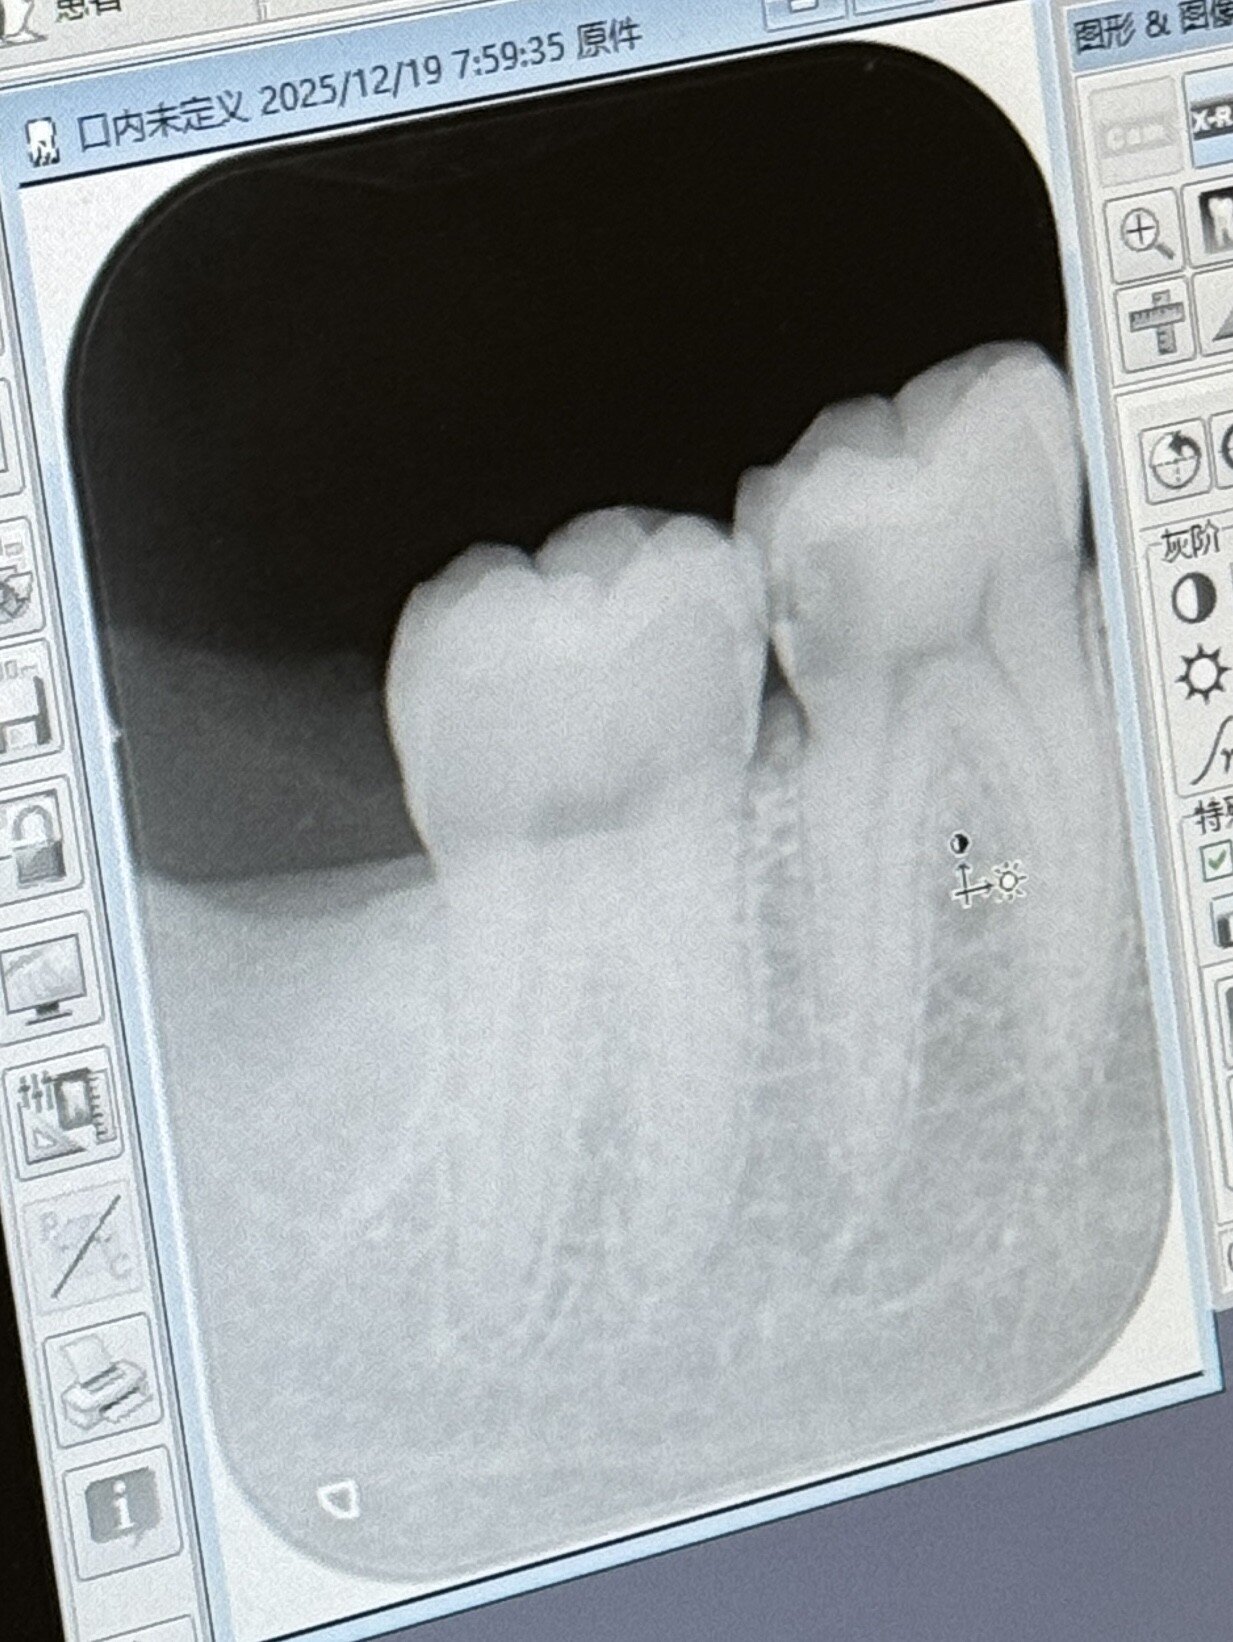

卧槽警惕邻面龋啊家人们,这两天右下磨牙有点疼,但是外观一点事没有,去医院看邻面龋已经蛀到牙神经了要做根管了。。。顺便推荐大家一个牙线,是宽的,很好用不会勒痛,薄荷味